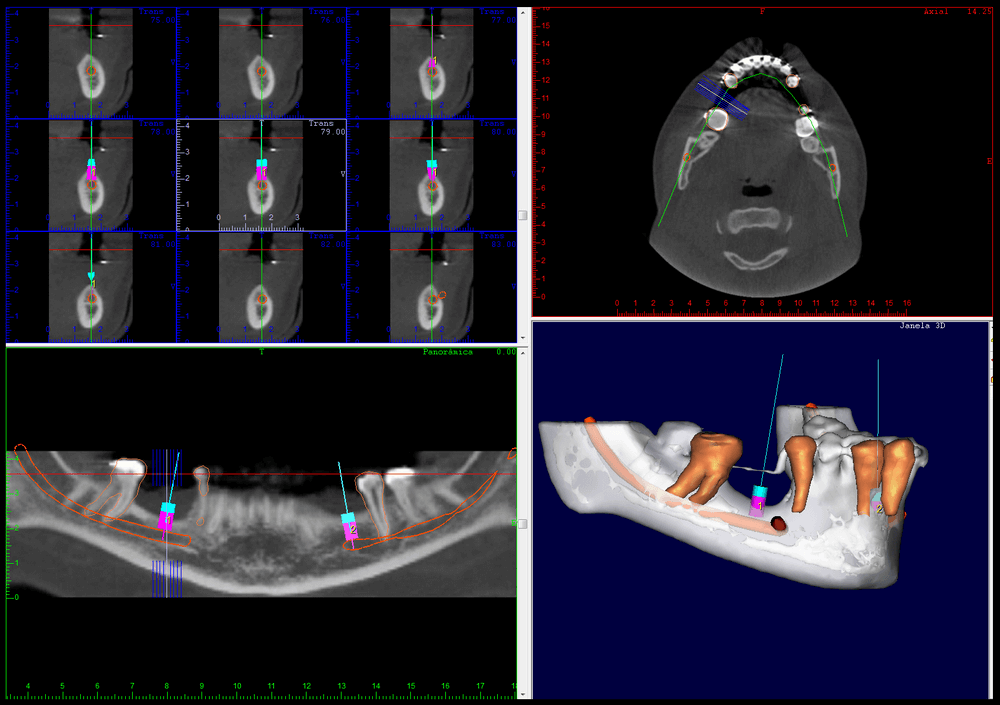

CIRURGIA GUIADA

É uma cirurgia realizada apenas com pequenas perfurações no tecido para instalar os implantes. A partir de um planejamento virtual realizado nos softwares específicos, é feita a confecção de guias cirúrgicas (técnica de prototipagem rápida) e, em seguida, há a transferência precisa do posicionamento dos implantes do computador para o paciente.